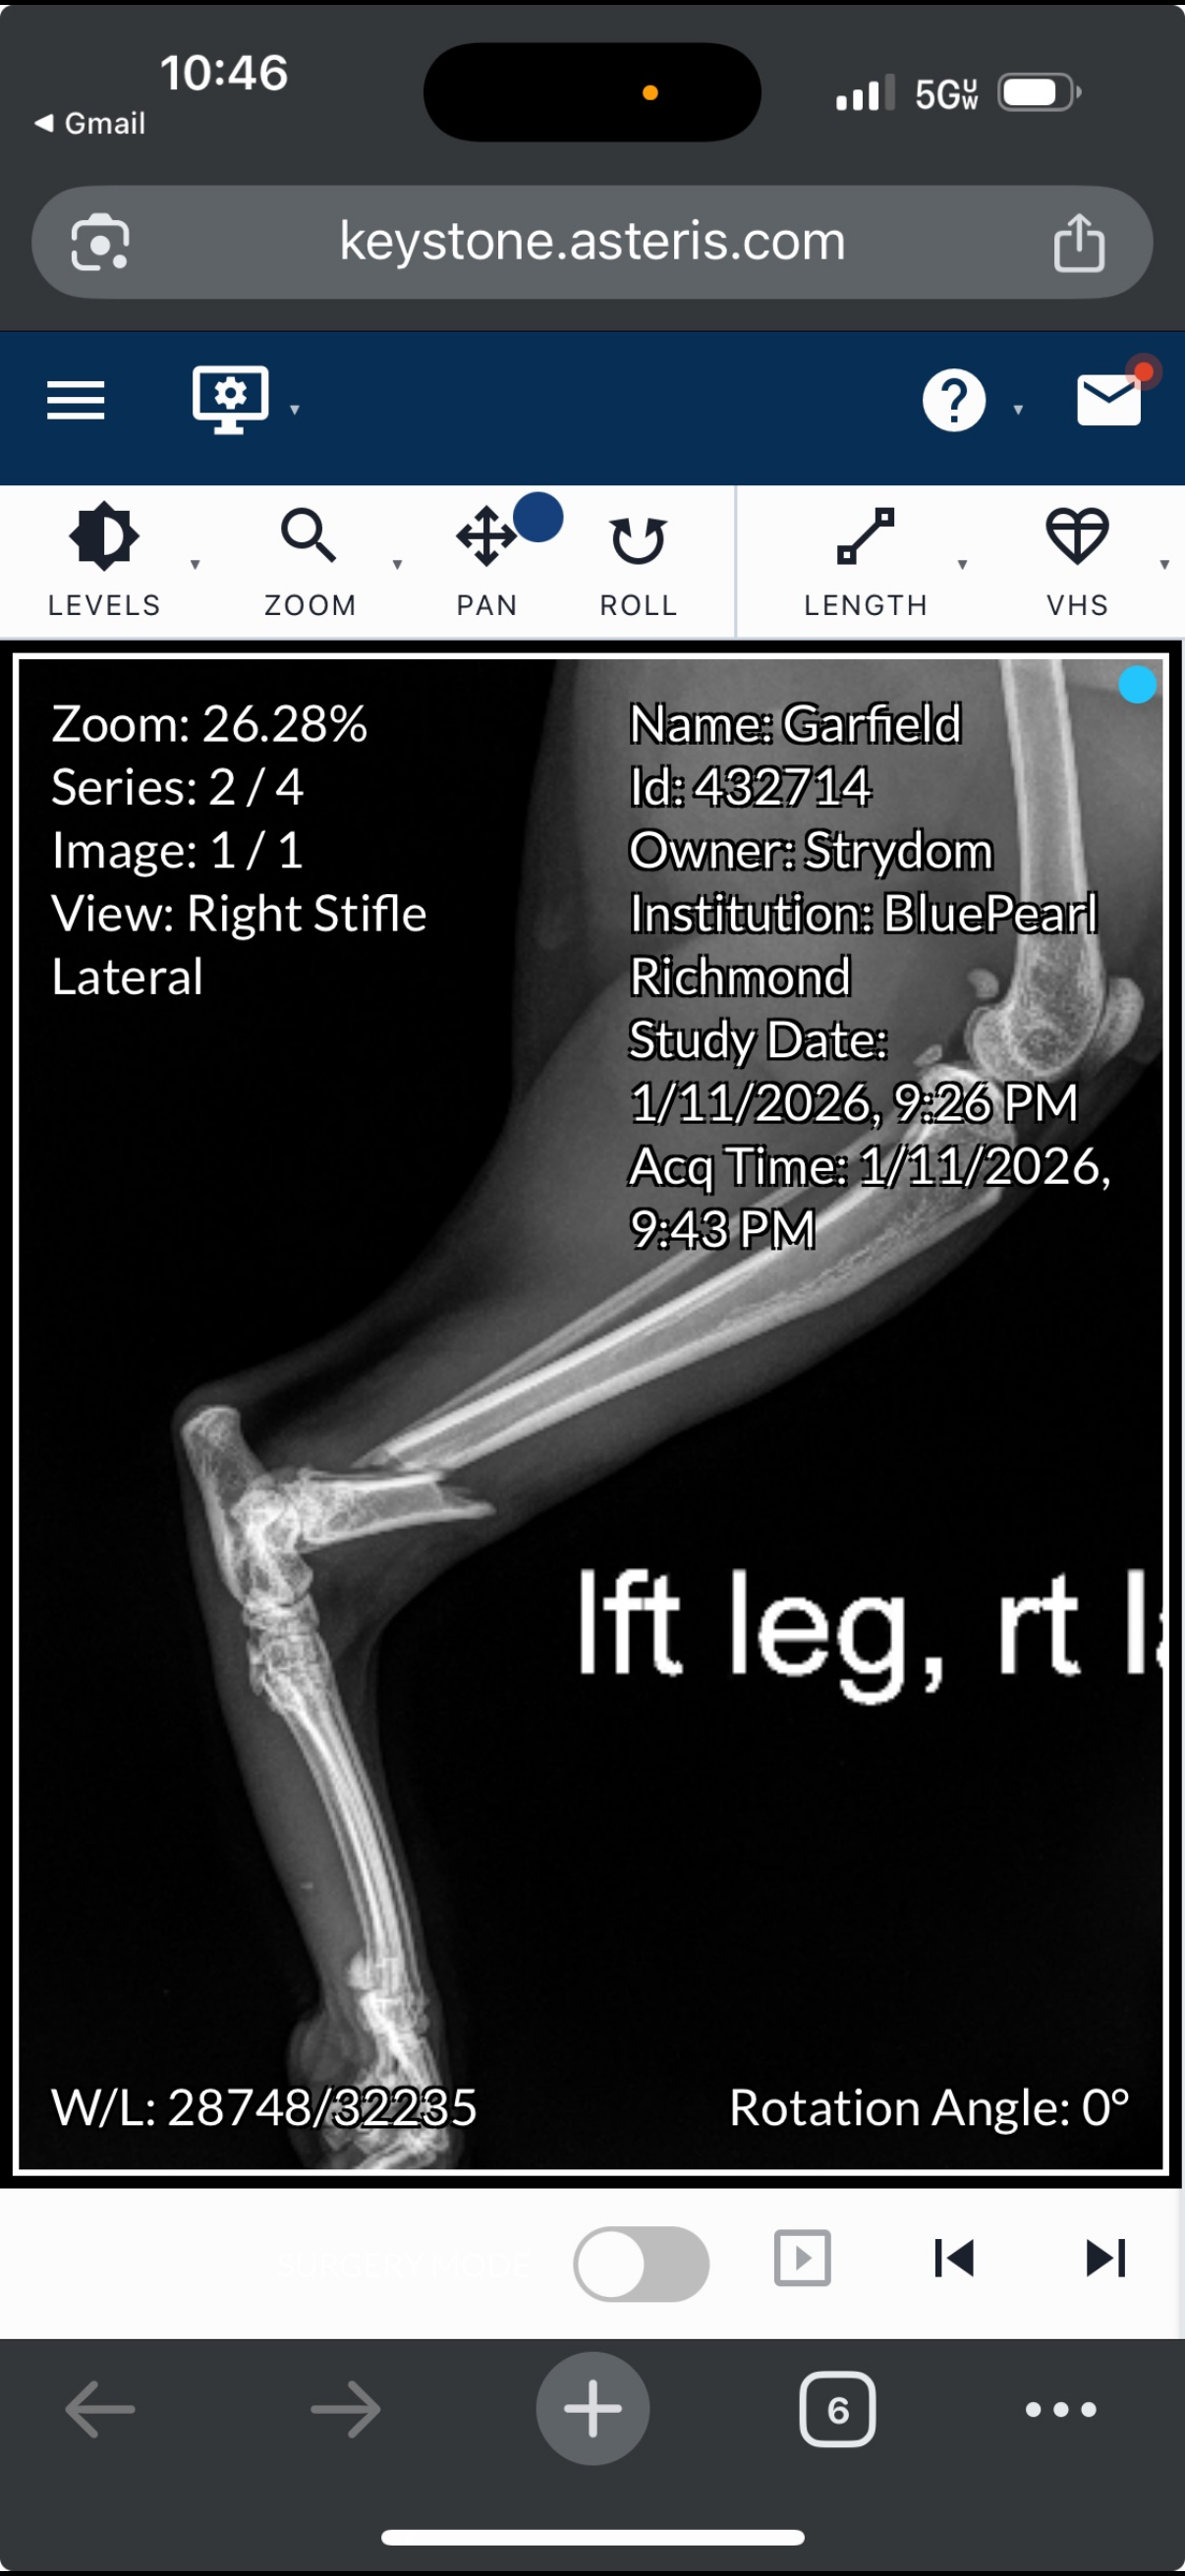

Our hearts are heavy right now. Garfield broke his leg on Sunday, 1/11/26, and underwent surgery on 1/16/26.

The vet bills for his care and recovery have been overwhelming — we’ve already paid over $6,000, with more costs still to come for follow-up visits, medications and physical therapy.